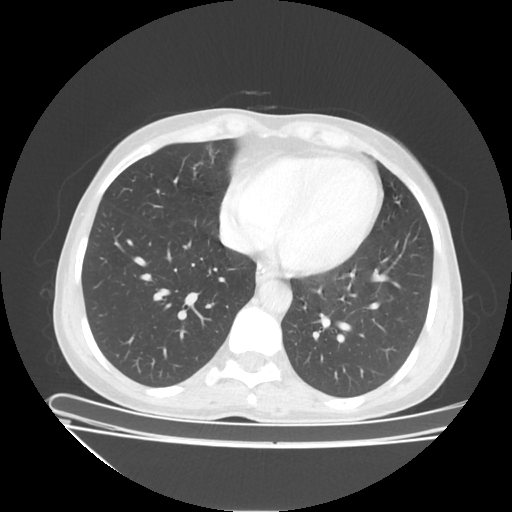

Reconstructed NATIVE CT scan (cycle consistency)

No window - Raw intensity values

Lung window (WL -600, WW 1500 β†’ Low βˆ’1350, High +150)

Mediastinum window (WL 40, WW 400 β†’ Low βˆ’160, High +240)